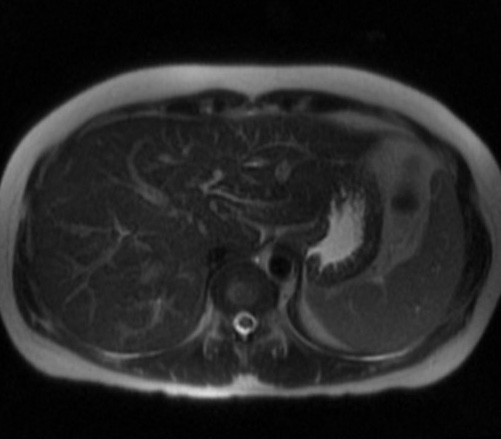

Image de voie

biliaire intrahepatique normale . IRM en T2 ,

coupe axiale . |

Aspect dilate des voies

biliaires intrahepatique avec calcul choledocienne :

ImIRM ponderee sur T2 , coupe axiale |